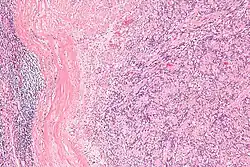

IPMs are diagnosed by examination of the tissue by a pathologist. They have a rim of peripheral lymphoid tissue (remnant of a lymph node) and consist of spindle cells with nuclear palisading. Red blood cell extravasation is common and blood vessels surrounded by collagen with (fine) peripheral spokes (amianthoid fibers) are usually seen.[2]

Immunostains for smooth muscle actin and cyclin D1 are characteristically positive. The main histologic differential diagnosis is schwannoma.

High mag.